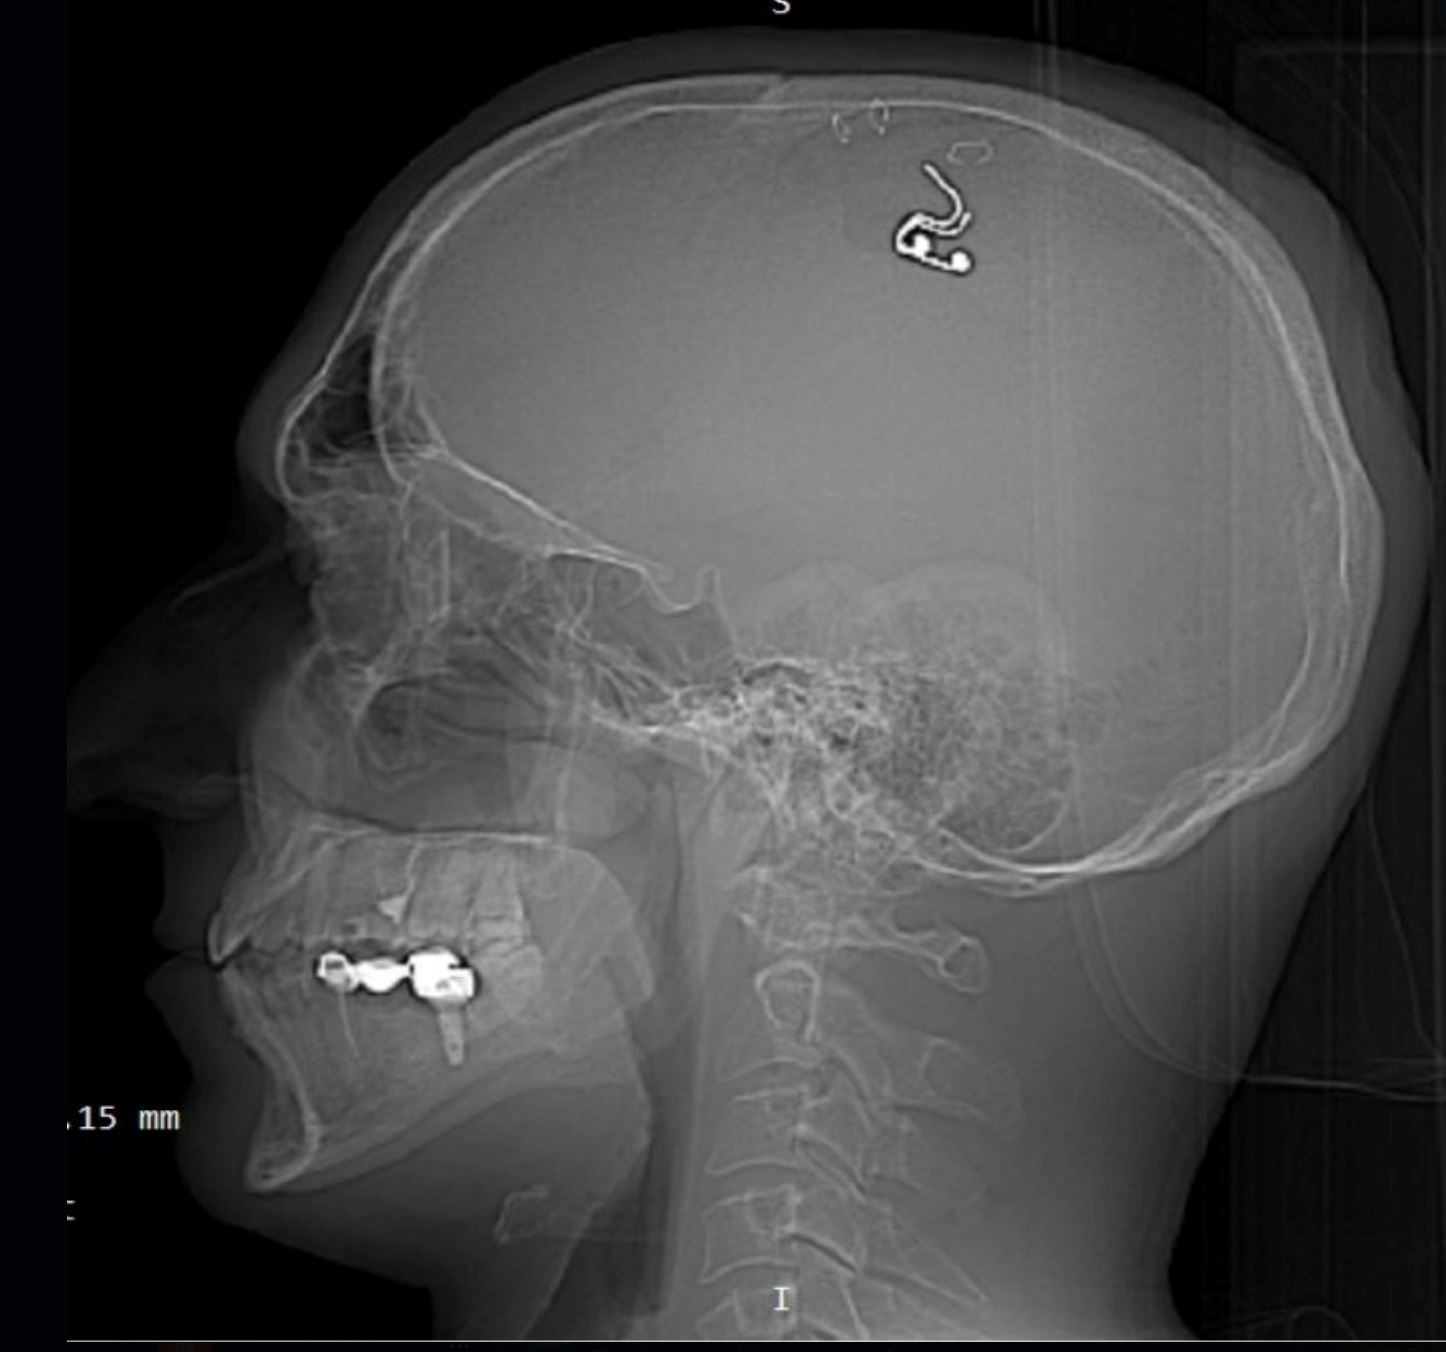

Disebabkan itu, seorang lelaki yang dikenali sebagai Mikhail Raduga, sanggup menebuk tengkorak kepalanya sendiri, dan memasukkan cip ke dalam otak bagi tujuan untuk mengawal mimpi.

BRAIN IMPLANT FOR LUCID DREAMING

For the first time in history, we conducted direct electrical stimulation of the motor cortex of the brain during REM sleep, lucid dreams, and sleep paralysis. The results open up fantastic prospects for future dream control technologies. pic.twitter.com/qypqV6ntyV